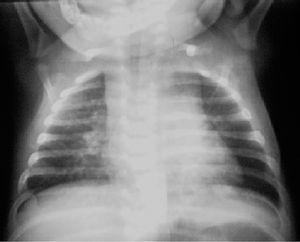

El niño ingresa por primera vez a las 5 semanas de vida por fiebre alta catalogándose de proceso neumónico. La radiografía de tórax identifica condensación alveolar retrocardíaca en lóbulo inferior izquierdo. Se instaura tratamiento antibiótico con ampicilina y cefotaxima durante 10 días. La radiografía de tórax de control previa al alta muestra mejoría radiológica.

Dos semanas después reingresa por persistencia de picos febriles. La radiografía de tórax presenta múltiples focos neumónicos asociados a ensanchamiento mediastínico (fig. 1).

Figura 1. Radiografía de tórax. Infiltrados pulmonares retrocardíaco izquierdo y en lóbulo superior derecho, ensanchamiento mediastínico e hilio derecho prominente.